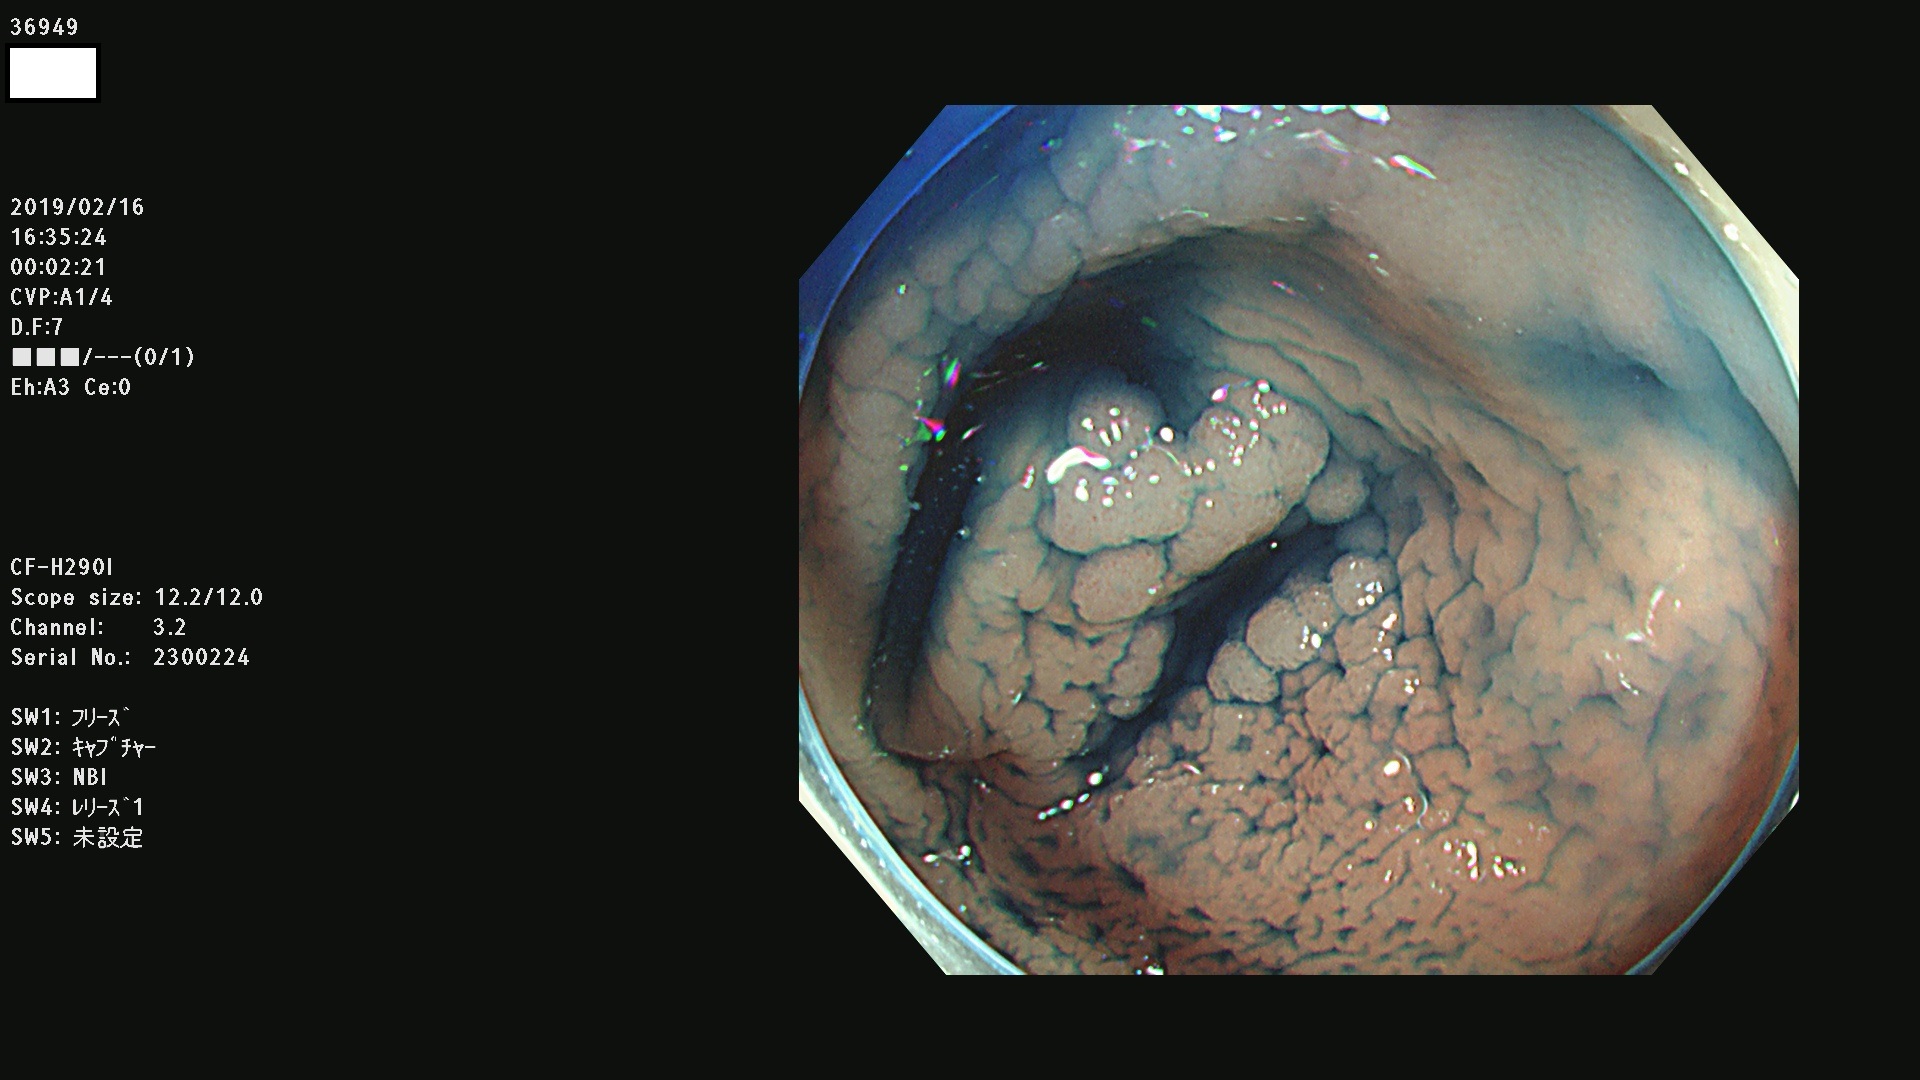

発見困難で危険性の高い平坦型病変(上記100名より抽出) ![]()